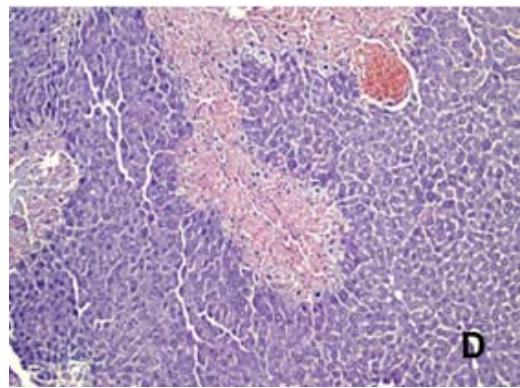

Na análise histológica, observou-se que o G2 (Tabela 1 e Figura 4B), que recebeu uma dose de APAP (500 mg/kg), apresentou necrose centrolobular multifocal, com predominância no escore 3 (3/6, $50\%$ ) ou seja, apresentando um nível de necrose de até $50\%$ do fígado. O G3 (Tabela 1 e Figura 4C) que recebeu pré-tratamento com silimarina (100mg/ Kg), demonstrou predominância nos escores 3 (2/6, $33,3\% )$ e 4 (2/6, $33,3\% )$, apresentando um nível de necrose hepático de

$50\%$ na maioria dos animais. O G4 (Tabela 1 e Figura 4D), que recebeu a dose de APAP $( 500 \mathrm { \ m g / k g ) }$ e pré- tratamento com EBUM (100 mg/Kg), exibiu predominância do escore 3 (4/6, 66,6%), mostrando um nível de necrose de até $50\%$ do fígado. O G5, que recebeu a dose de APAP (500mg/kg) e pré-tratamento com EBUM (500 mg/Kg), houve predominância do escore 2 (4/6, 66,6%), (Tabela 1 e Figura 4E), com um nível de necrose hepática igual ou inferior a $25\%$.

Escore 0 (sem necrose); escore 1 (necrose $< 10\%$ do fígado); escore 2 (necrose entre $10 \mathrm { - } 25\%$ do fígado); escore 3 (necrose entre $25 \mathrm { - } 50\%$ do fígado); escore 4 (necrose $> 50\%$ do fígado). Esses resultados podem ser visualizados na Figura 4, que inclui fotomicrografias representativas e a porcentagem de área de necrose hepática.

FAnálisehistopatológicao tecido hepáticocamundogos Swiss intoxicados codosúicaacetaminof iotatagtiai çõot ivtoopticaqãt quantoFieesentauotivamenteagns fora corada hematoxilina e eosina (HE) e capturadas com um aumento de $100 \times$.